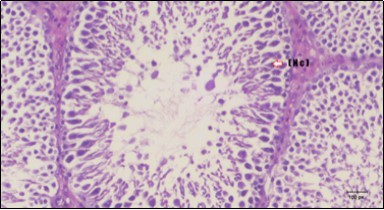

Histological examination of control rats' testis showed normal histological structure of the seminiferous tubules with an increase in the spermatogonia and other spermatocytes compared with the diabetic rats which showed an obvious decrease in the count of germinal cells generally and sloughing of germ cell in the lumen of seminiferous tubules in addition to absence of the mature sperms (Figure 3 and Figure 4). Rats tested of Fenugreek group and those treated with Glimepiride (Figure 5 and Figure 6) presented an increase in the number of spermatogenic cells and mature sperms with few focal necrotic cells. Whereas the combination therapy group showed normal histological structure of the seminiferous tubules with normal spermatogonia, presence of ledying cells and more mature of sperms (Figure 7). STZ reduced testosterone production, suggesting a decrease in the function of both Leydig (testosterone producing cell) and Sertoli (spermatogenesis) cells, which might be caused by a reduction in insulin secretion. These changes are probably due to increased Reactive Oxygen Species (ROS) production by accelerated Advanced Glycation End Products (AGE) formation 31 hexosamine and Protein Kinase C pathway. The administration of Fenugreek seeds to diabetic rats significantly decrease of sperm shape abnormality and improve the sperm count 32. Glimepiride reduced sperm abnormality and increased testis weights and sperm count by its antioxidant action 30. The potential protective efficacy of Fenugreek seed extract when added to Glimepiride was observed on reproductive systems.

Figure 4.Photomicrogragh of testis section of diabetic rat showing the sloughing of germ cells towards lumen of seminiferous tubules, absence of spermatozoa with low height of germinal epithelium and congested wide interstitial tissue (star). (H&E) (40x).

Figure 6.Photomicrogragh of testis section of treated rat showing increased number of spermatogenic cells from spermatogonia till spermatozoa (star). Few liquid infiltration in wide interstitial tissue (H&E) (40X).